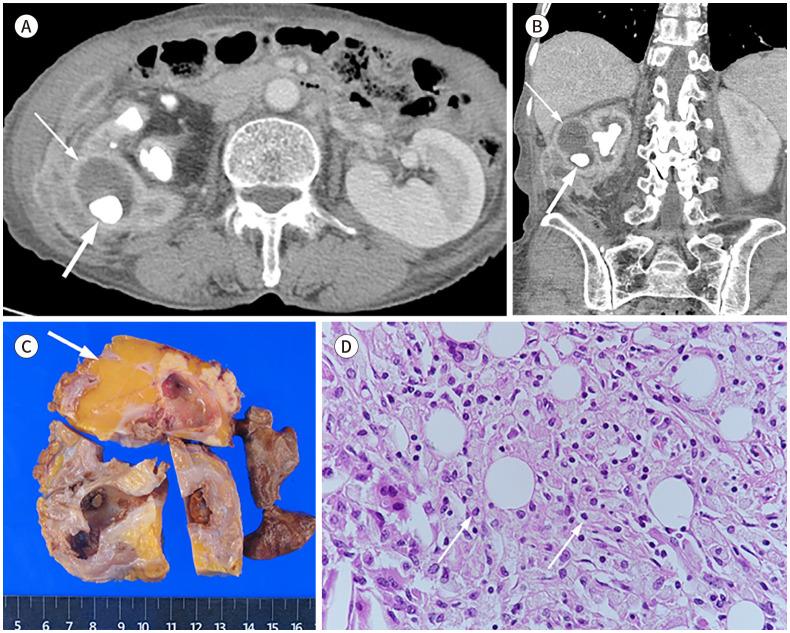

Xanthogranulomatous (XG) inflammatory disease is a rare benign disease involving various organs, including the gallbladder, bile duct, pancreas, spleen, stomach, small bowel, colon, appendix, kidney, adrenal gland, urachus, urinary bladder, retroperitoneum, and female genital organs. The imaging features of XG inflammatory disease are nonspecific, usually presenting as a heterogeneous solid or cystic mass. The disease may also extend to adjacent structures. Due to its aggressive nature, it is occasionally misdiagnosed as a malignant neoplasm. Herein, we review the radiological features and clinical manifestations of XG inflammatory diseases in various organs of the abdomen and pelvis.

黄色肉芽肿性(XG)炎性疾病是一种罕见的良性疾病,可累及包括胆囊、胆管、胰腺、脾脏、胃、小肠、结肠、阑尾、肾脏、肾上腺、脐尿管、膀胱、腹膜后间隙及女性生殖器官在内的多个器官。XG炎性疾病的影像学特征不具有特异性,通常表现为不均匀的实性或囊性肿块。该疾病也可能蔓延至相邻结构。因其具有侵袭性,偶尔会被误诊为恶性肿瘤。在此,我们回顾腹部和盆腔各器官XG炎性疾病的放射学特征及临床表现。